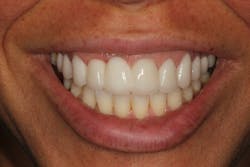

Reduction in quantity and quality of bone can also compromise functional and esthetic outcomes of both implants and fixed bridge restorations (figures 3 and 3a).

• Site development to increase hard and soft tissue for pontic sites in fixed bridge prosthetics (figures 4–4e)